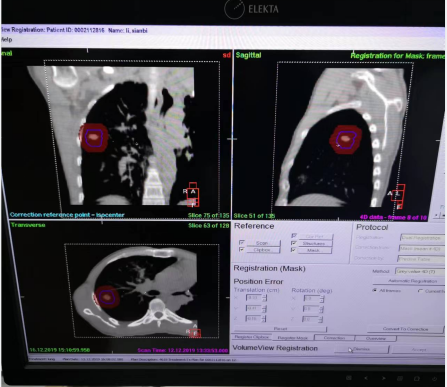

4. 加速器上治疗时,确保患者体位和ABC的连接方式与扫描CT时一致。患者一只手握住门控开关,戴一副折射眼镜(患者在治疗时可以同步看到电脑系统的提示内容),在达到当时训练时设置的吸气阈值时开始屏气,加速器出束前先进行影像验证(CBCT)确保体位的准确性。